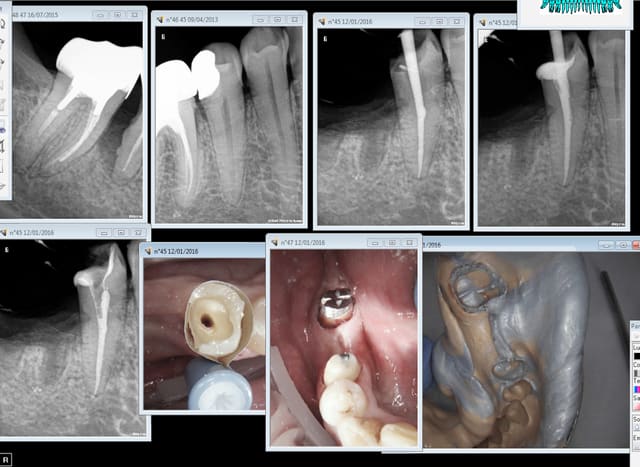

C'est pas fini vos conneries ? J'ai voulu poser un bridge aujourd'hui de 45 à 47 et la 17 est descendue de 2 mm en une semaine ( pas la 16 va comprendre) du coup endo de 17 et lifting occlusal. -))))

Sur la prémo c'est un coup de foret ou une petite résorption interne?

Pourquoi la bio sur la 45 ! La pauvre.

Et la 17 aussi :P

(je pense connaitre la réponse : pour mettre un inlay core ? :D)

La bio c'est avant ou après le bridge. Je préfère la faire avant. -)))

A 122,55 ( CMU) ca va pas non ? Il faut penser à son ratio SPR57/ SC33 on ne va pas gâcher un ic pour si peu. -)))

Pour la 17 l'ortho c'est pas remboursé après 16 ans , l'endo si. -)))

la 45 y avait la marge pour la tailler vivante non ? :D

Apèrs la 17 difficile de dire si une coronoplastie ou un onlay n'aurait pas suffit :P mais ça c'est Hors nomencalture dans notre beau système :D

Avec une ( bonne) endo pas d'emmerdes à court terme genre sensibilité chaud- froid..... tu penses bien que c'est pas pour ce que va me rapporter l'endo et le SC 33 sur 45 que j'ai choisi cette option. -)